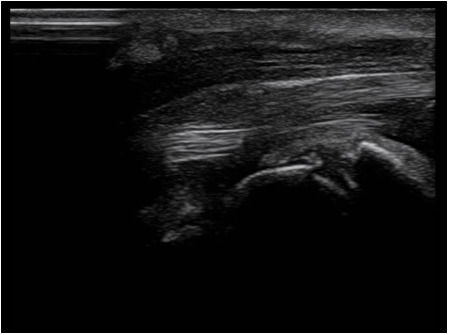

Se sigue clínica y ecográficamente a la paciente en consulta. Se comprueba mediante ecografía la liberación del nervio mediano con la segunda intervención, acompañada de la ausencia de sintomatología en la paciente.

Mediante la ecografía en Atención Primaria es posible observar un atrapamiento del nervio mediano, tanto en un primer diagnóstico como en caso de una falta de efectividad de una cirugía acelerando los tiempos de espera.